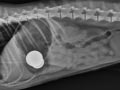

Keracunan Mineral Seng (Zinc) Pada Anjing Keracunan Mineral Seng (Zinc) Pada Anjing (0 komentar)

29 September 2014 - 21:44

Mineral seng merupakan salah satu mineral yang sangat penting untuk pemeliharaan tubuh, akan tetapi..., selengkapnya.